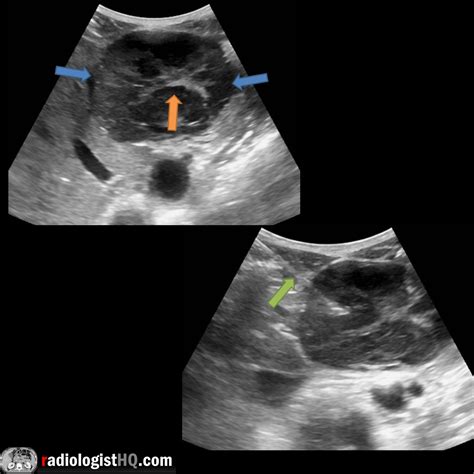

• Ultrasound: This non-invasive test uses sound waves to create images of the liver. It can detect the presence of a nodule but may not provide enough detail to confirm FNH.